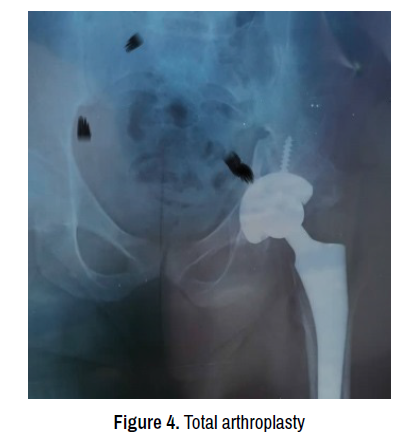

The results of the 9 operated patients were satisfactory after hip arthroplasty; we believe we made the best choice by immediately proposing a hip arthroplasty (Figures 3 and 4).

trauma-treatment-arthroplasty

Figure 4. Total arthroplasty